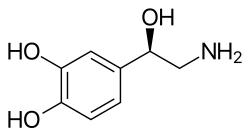

Noradrenaline system

The noradrenaline system consists of around 15,000 neurons, primarily in the locus coeruleus.[12] This is diminutive compared to the more than 100 billion neurons in the brain. As with dopaminergic neurons in the substantia nigra, neurons in the locus coeruleus tend to be melanin-pigmented. Noradrenaline is released from the neurons, and acts on adrenergic receptors. Noradrenaline is often released steadily so that it can prepare the supporting glial cells for calibrated responses. Despite containing a relatively small number of neurons, when activated, the noradrenaline system plays major roles in the brain including involvement in suppression of the neuroinflammatory response, stimulation of neuronal plasticity through LTP, regulation of glutamate uptake by astrocytes and LTD, and consolidation of memory.[13]

The dopamine or dopaminergic system consists of several pathways, originating from the ventral tegmentum or substantia nigra as examples. It acts on dopamine receptors.[14]

Parkinson's disease is at least in part related to dropping out of dopaminergic cells in deep-brain nuclei, primarily the melanin-pigmented neurons in the substantia nigra but secondarily the noradrenergic neurons of the locus coeruleus. Treatments potentiating the effect of dopamine precursors have been proposed and effected, with moderate success.